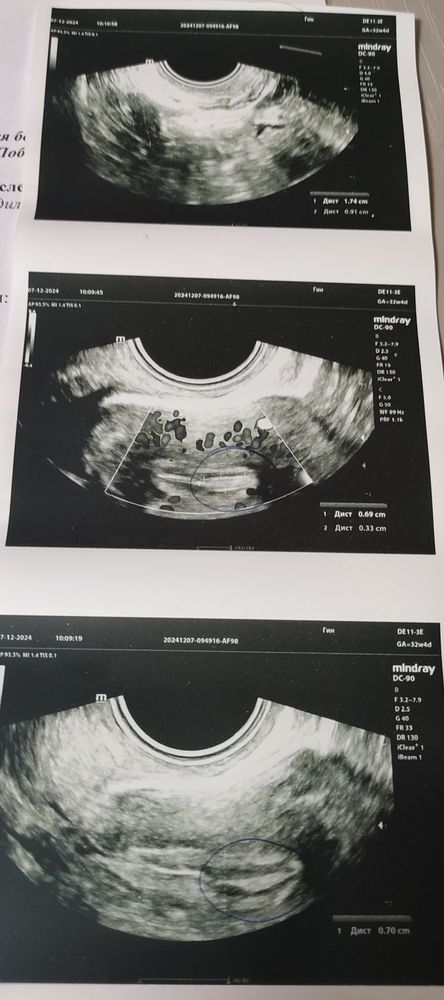

Тут прерывистая линия. Поэтому подумали на полип.

Если нет жалоб, то можно подождать . полипы до 1см самостоятельно могут оторваться и выйти с месячными… либо это не полип вовсе, а складка эндометрия.